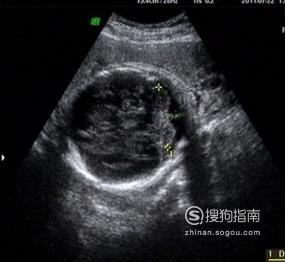

体重(克):约2.75千克 身长(cm):从头部到臀部长约34厘米 双顶径(cm):8.81士0.57 腹围(cm):29.44士2.83 股骨长(cm):6.95士0.47

羊水指数范围(cm):15.5-15.6 羊水量正常值(ml):1000-1500 胎盘成熟度:胎盘1级 孕酮值(HCG:iu/ml):3,640 - 117,000 宫高(cm):29-36.5 腹围(cm):86- 98 体重增长(kg):10

本周去医院产检,医生会要求你去做一次黑白B超,重点在于明确宝宝是否有脐带绕颈现象、目前的入盆情况、预估胎儿体重等以确定分娩方式。这个时候有的宝宝已经有六七斤了,长势喜人啊!也有些宝宝才四斤左右,别担心,最后的一个月TA会给你个大惊喜。